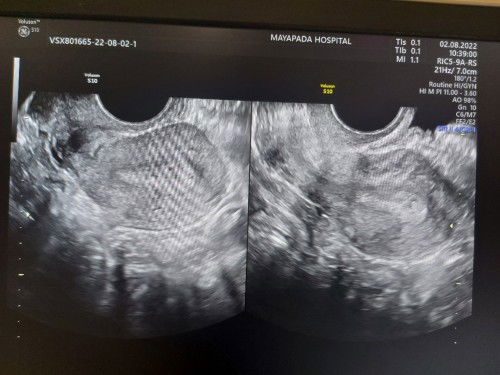

Mom ini kehamilan pertamaku udah 2 hari dirawat di rs karena sempet ngeflek kecokelatan dan kondisinya khmilannya 5 minggu dan udh trlihat kantung Udah d minumin obat dan dpt infusan penguat kandungan Hari ini sempet kluar darah merah dan sdkit gumpalan, perutku bbrp kali sakit di bagian bawah dan punggung belakang bawah Aku sempat khawatir dan nangis krn takut dan kesakitan mom.. tapi dokter masih menyuruh bedrest seminggu di rs.. bnr2 ga blh banyak gerak, cuma d kasur dan buang air jg di pispot mom.. soalnya gerak dkit jg sakit 🥲 Dan selama darah yg keluar tidak deras msh ada harapan. Dan aku mohon doanya moms supaya kehamilanku dan debaynya sehat sehat dan terselamatkan. . Aamiin #firstbaby #pleasehelp #doa #flek